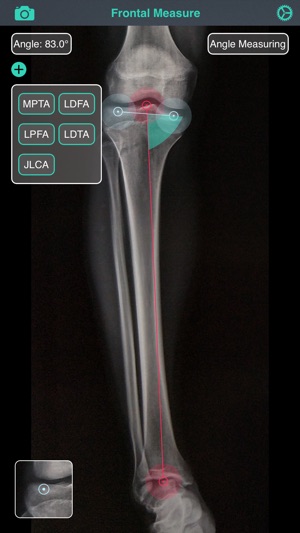

敘述:Measuring tool for lower limb

Features:

Measuring for:

- Anatomical or mechanical axis in frontal or sagittal plane, ex: MPTA, LDFA, LDTA, PPTA, TBVA, JLCA... etc

- The percentage of weight bearing line

- Length

- Tibial slope